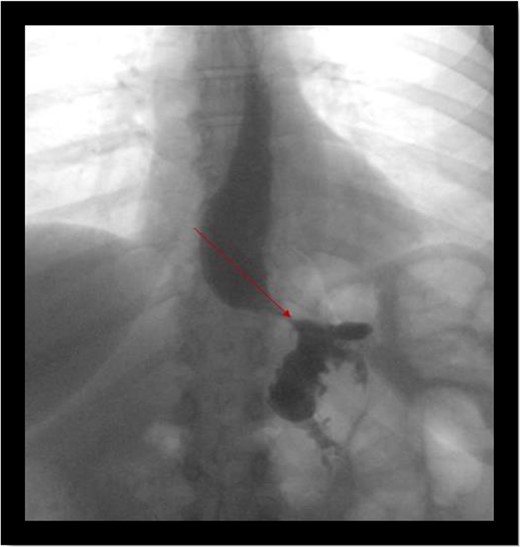

A 49-year-old female who was status post laparoscopic gastric bypass at an outside facility in 2010 presented to our bariatric clinic for evaluation. She lost 99 lb in 2 years after her gastric bypass but regained 43 lb in a couple of months prior to presentation. At the time of evaluation, patient’s BMI was 32. Upper gastrointestinal swallow study was negative for any acute abnormality (Fig. 1). Endoscopic gastroduodenoscopy (EGD) was performed which showed a communication between the gastric pouch and remnant stomach (Fig. 2). Gastric pouch was found to be 5 cm from the GE junction.